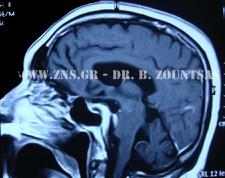

Μηνιγγίωμα

Ολική εξαίρεση μηνιγγιώματος πτέρυγας σφηνοειδούς